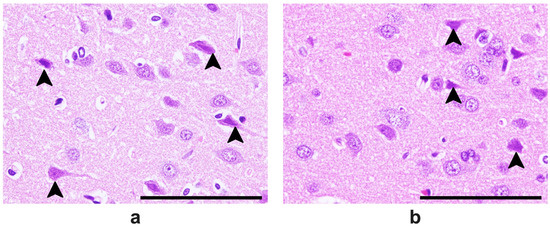

2.5. Results of the Histopathological Analysis of Brain Tissues

4.4.5. Histopathological Analysis of Brain Tissues